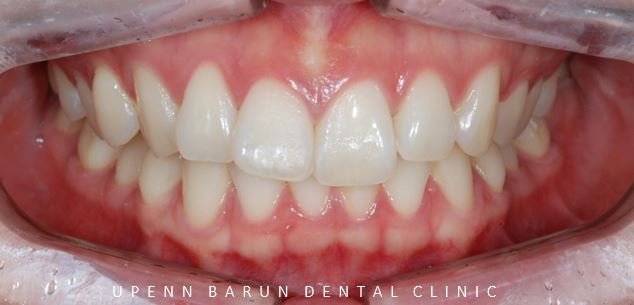

치료 전 사진

교정 전 구내사진

먼저 인비절라인을 시작하기에 앞서

구내 사진을 찍어보았습니다.

정면에서 보았을때

앞니 두개의 모양과 길이만 달라보였으나,

측면 사진을 보니 앞니가 튀어나와 뻐드러져 있고

교합면에서 바라봤을때는 치아끼리 이은 선이

삐뚤빼뚤한 양상을 보였습니다.